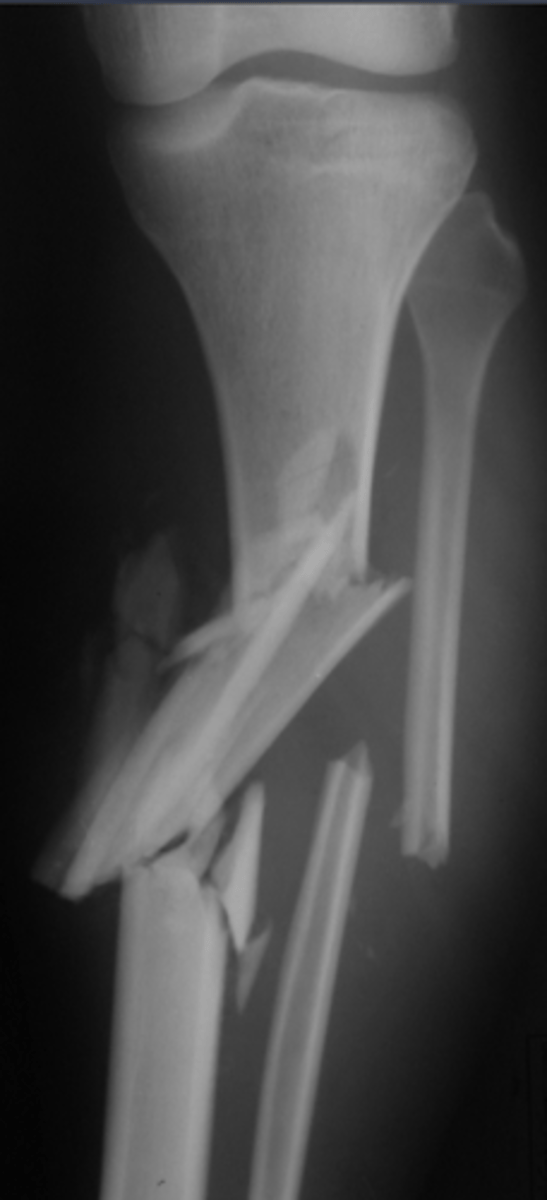

________ fractures = multi-fragment (3+ pieces)

Comminuted

Dislocations (i.e., at proximal/distal joint + accompanying fractures)

What is a "Monteggia fracture"?

Ulnar fracture --> dislocation of radio-humeral joint

What is a "Galeazzi fracture"?

Fracture of the radius and the dislocation or subluxation of the DRUJ